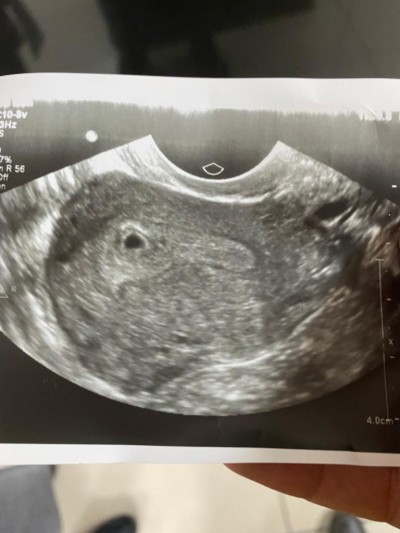

İki tane kese mi var anlayan var mı

Kızlar son adet tarihime göre 5+4 günlüğüm 5 gün önce doktorum vajinal ultrasonla baktığında keseyi gördü ben pek anlamıyorum da gerçekten bilen biri yorumlayabilir mi kese kaç santim bide dediğim gibi pek anlamıyorum iki kese mi var ben mi yanlış görüyorum biri sağda biri solda bakar mısınız

Yalnızca solda bir kese var. Kesenin kaç mm olduğu da ultrason kağıdında yazar. Yazılı kısımları çekmemişsiniz ki kaç mm olduğu sizlik bir durum değil. Bir sorun olsaydı doktor zaten söylerdi size. Söylememişse bir sorun yok demektir.

Sağ tarafta da bı tane var sandım orasida karanlık ya bide yeni bı foto ekledim haftama göre nasıl kese merak ettim sadece

İki kese görünmüyor bence

Ben ikizlere hamileyim benim ultrason fotoğraflarından çok farklı geldi bana

1 tane kese var cnm

Sağdaki kısım rahimde değil. Rahim, orta kısımda armut şeklinde bir yapı var orası.

Yok canım 1 kese var

Kesen 1 cm canim daha bebek de tek ikiz olsa doktorun söylerdi